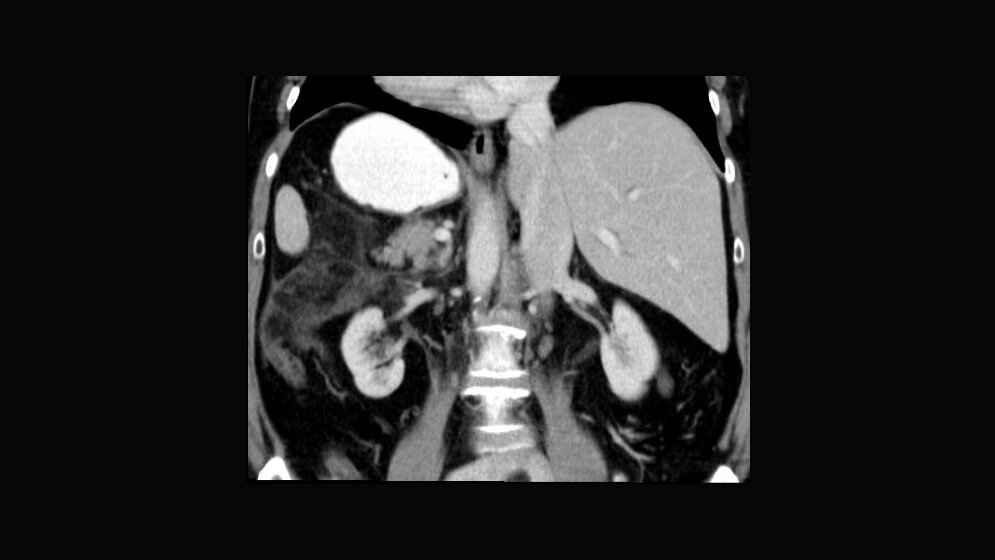

Die Ätiologie des Situs inversus totalis ist unklar. Isoliert vorkommend ist er bei Neugeborenen und auch Erwachsenen asymptomatisch.

Schlüsselwörter: Situs inversus totalis, Röntgen, CT, MRT

The etiology of situs inversus totalis remains uncertain. Isolated situs inversus totalis is usually asymptomatic in the neonate and adults.

Keywords: Situs inversus totalis, x-ray, CT, MRI